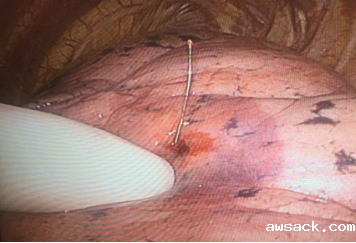

三、肺小结节术前穿刺定位术

胸外科联合CT室共同完成,为国内先进的术前定位技术。为肺内微小病灶手术治疗提供了巨大助力,提升了微创手术治疗肺部小结节的手术适应征,为早期肺癌患者带来福音。